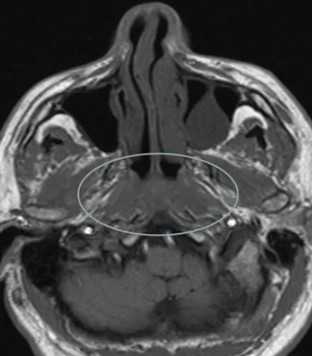

С помощью КТ сложно было выявлять опухоли малых размеров (Т1стадия) и их границы в результате низкой контрастности, а также новообразования с поверхностным распространением (рис. 1). Вместе с тем, 72,0% обследованных больных имели Т3, Т4 стадии опухолевого процесса и после болюсного введения контрастного вещества контрастность опухоли повышалась. С увеличением размера опухоли отмечалась неоднородность усиления из-за наличия некроза (рис. 2). Жировые пространства подъязычной области в нормальном состоянии представляют собой симметричную зону низкой плотности между челюстно-подъязычной и подбородочно-подъязычной мышцами. Облитерация жировых пространств подъязычной области служила основным показателем опухолевого поражения при выявлении небольших образований дна полости рта (рис. 3,4).

Рис.1. Пациент Ж., 58 лет. МСКТ ротоглотки в аксиальной проекции: А - нативное исследование, В - с внутривенным болюсным контрастированием. Небольшая инфильтративная опухоль ротоглотки (левой небной миндалины Т1 стадии). Границы опухоли не дифференцируются, накопление контраста слабое (показатели плотности в нативной фазе исследования 45 ед.Н, после внутривенного болюсного усиления - 56 ед.Н). Определяется смещение левой стенки ротоглотки, сглаженность контура (стрелки)